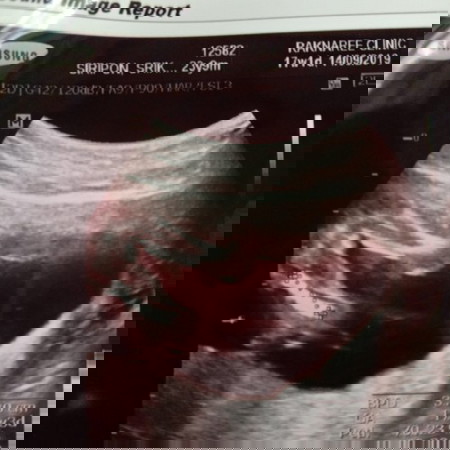

เพศลูก

แบบนี้ผู้ชาย หรือผู้หญิงค่ะ

น่าจะ ผญ นะคะ แต่ยังไม่ชัดเท่าไหร่ รอดูซาวครั้งน่าถ่าเหนเปน 2 ขีด เปนผญ ค่ะ🥰

น่าจะผู้หญิงนะคะ รอซาวด์อีกทีน่าจะชัดกว่านี้

เราเห็นเหมือนจะเป็นจู๋เลยค่ะ

น่าจะญ.นะค่ะ มีกลีบเล็กๆๆ

ชายค่ะ เหมือนบ้านนี้เลย